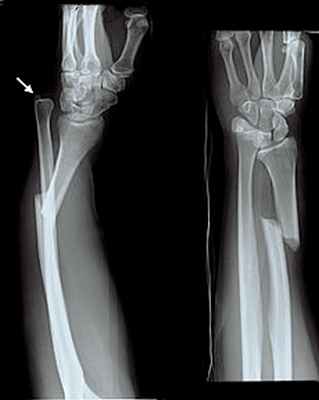

Перелом лучевой кости с вывихом головки локтевой кости (перелом Галеацци) • Причины: падение на вытянутую руку, удары по предплечью • Патоморфология: лучевая кость ломается в нижней трети, её отломки смещаются кпереди (дистальный отломок дополнительно занимает положение пронации из-за сокращения мышц), образуя угол, открытый кзади; головка локтевой кости смещается в ладонную или тыльную сторону • Клиническая картина: характерная деформация (западение на тыльной поверхности предплечья с лучевой стороны и выпячивание на ладонной), искривление оси лучевой кости, пальпируется головка лучевой кости на локтевой стороне лучезапястного сустава, болезненность при пальпации и осевой нагрузке. Надавливание на головку лучевой кости вызывает вправление, при прекращении давления головка снова вывихивается. Необходимо проводить в обязательном порядке рентгенографию с захватом лучезапястного сустава • Лечение: репозиция, гипсовая повязка на 8–10 нед, при неэффективности консервативного лечения — открытая репозиция и остеосинтез лучевой кости, открытое вправление головки локтевой кости.